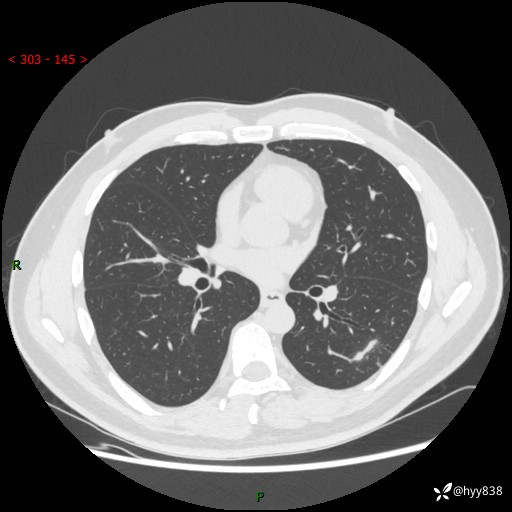

中年男性,胸闷3月余。多发团片、肺小叶分布、空气支气管征、明显强化---结果公布~

现病史:患者3月前出现胸闷,卧位时加重,坐位时缓解,无咽痛、咳嗽,无头痛,无全身酸痛,无结膜充血,无胸痛、心慌,无咯血,无呼吸困难,无咳痰,2024-07-02于当地市第一民医院行胸部CT,结果不详,2024-07-05就诊于我院急诊内科,行胸部CT同时增强,结果示:左肺下叶多发结节灶,考虑感染可能。今患者为求进一步诊治来我院,门诊以“肺部感染”收入我科。 患者本次起病来精神、食欲、睡眠尚可,大小便可,体力,体重无明显变化。

胸部CT平扫+增强

各期CT值:30hu 90hu 77hu